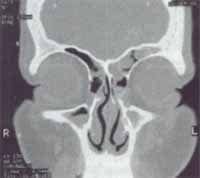

Figura 10. Tomografía computarizada en paciente con sintomatología rinosinusal recurrente con desviación aparentemente poco significa-tiva y cornete inferior buloso.